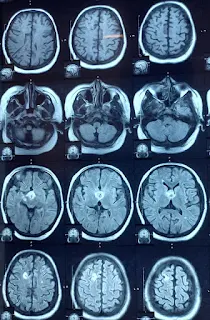

This 17 years female, underwent ETV and insertion of VP shunt in May 31,2022, presented with the complaints of headache with vomiting and blurring of vision for two months, symptoms improved after surgery. Patient has no previous history of radiation and chemotherapy. On clinical examination patient is oriented with time, place and person has no obvious deficits.MRI Brain with contrast April 16,2022 shows a complex supra Sellar mass reaching up to the foramen of Monro and causing asymmetrical dilation of lateral ventricle, suggestive of hypothalamic glioma.